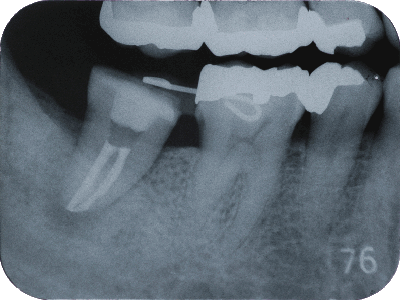

根管治療では、マイクロスコープを活用し、肉眼では確認できない根管内部の細部まで視認しながら処置を進めます。根管は複雑な形状をしており、細菌が残ると再感染のリスクが高まります。そのため、根の先端まで徹底的に清掃し、緻密な充填を行うことで、治療後の安定性を高めています。根の病変による痛みや違和感がある場合にも、適切な診断と精密な処置を行い、歯の保存を目指します。